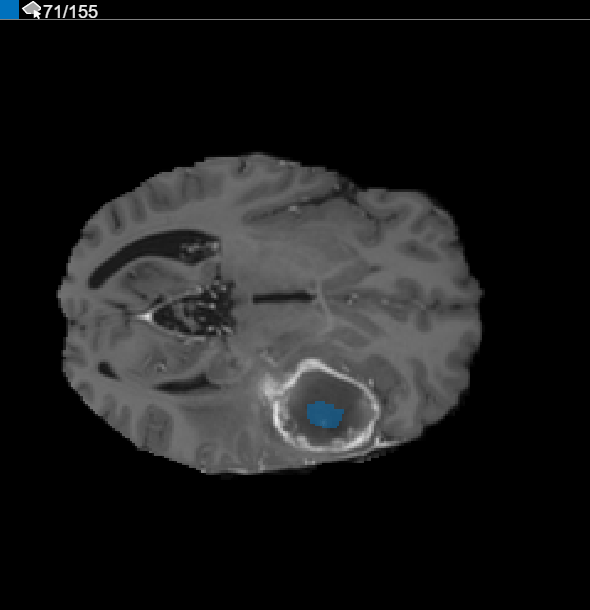

After using interpolation, check the individual slices to see if the interpolation created satisfactory ROIs. Note that the ROI on slice 71 does not fill the entire object that you want to segment. You can manually adjust the ROI using the Paint Brush tool. Alternatively, you can use one of the tools in the Automate tab. For example, you can use Active Contours to grow the ROIs on the slices where it does not fill the full size of the tumor.

In the Slice pane, navigate to the slice where the object first appears and start labeling the object on each slice using a drawing tool. In the following figure, this example uses the Paint Brush tool to label the tumor. As previously, you can draw the object on each slice where it appears or use the interpolation tools to draw on multiple slices automatically. After interpolation, you can use drawing tools, such as the Eraser, to modify the automated segmentation on each slice.